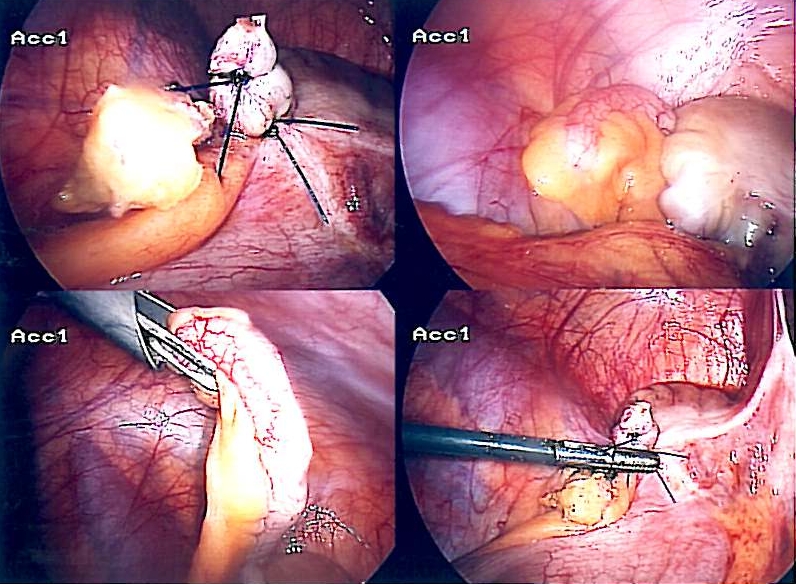

충수 절제술은 개복 수술 또는 복강경 수술을 통해 수행할 수 있다. 복강경 충수 절제술은 급성 충수염에 대한 중재로서 개복 충수 절제술보다 여러 가지 장점이 있다.[89]

복강경 충수 절제술은 1983년에 도입되었으며 급성 충수염에 대한 점점 더 널리 사용되는 중재술이 되었다.[93] 이 수술 절차는 복부에 각각 약 0.64cm 에서 약 1.27cm 길이의 세 개에서 네 개의 절개를 가하는 것으로 구성된다. 이러한 유형의 충수 절제술은 복강경이라고 하는 특수한 수술 도구를 절개 부위 중 하나에 삽입하여 수행된다. 복강경은 환자의 몸 외부의 모니터에 연결되어 외과의가 복부의 감염된 부위를 검사하는 데 도움을 준다. 나머지 두 개의 절개는 수술 도구를 사용하여 충수를 제거하기 위해 만들어진다. 복강경 수술에는 전신 마취가 필요하며 최대 2시간까지 걸릴 수 있다. 복강경 충수 절제술은 개복 충수 절제술에 비해 수술 후 회복 기간 단축, 수술 후 통증 감소, 얕은 수술 부위 감염률 감소 등 여러 가지 장점이 있다. 그러나 복강경 충수 절제술에서는 복강 내 농양 발생이 개복 충수 절제술보다 거의 3배 더 흔하다.[94]

소아 환자의 경우, 맹장의 높은 이동성으로 인해 충수를 제대(배꼽)를 통해 체외로 꺼낼 수 있으며, 전체 시술을 단일 절개로 수행할 수 있다. 복강경 보조 경 제대 충수 절제술은 비교적 최근에 등장한 기술이지만, 많은 사례가 보고되었으며 수술적 및 미용적 결과가 매우 좋다.[95]